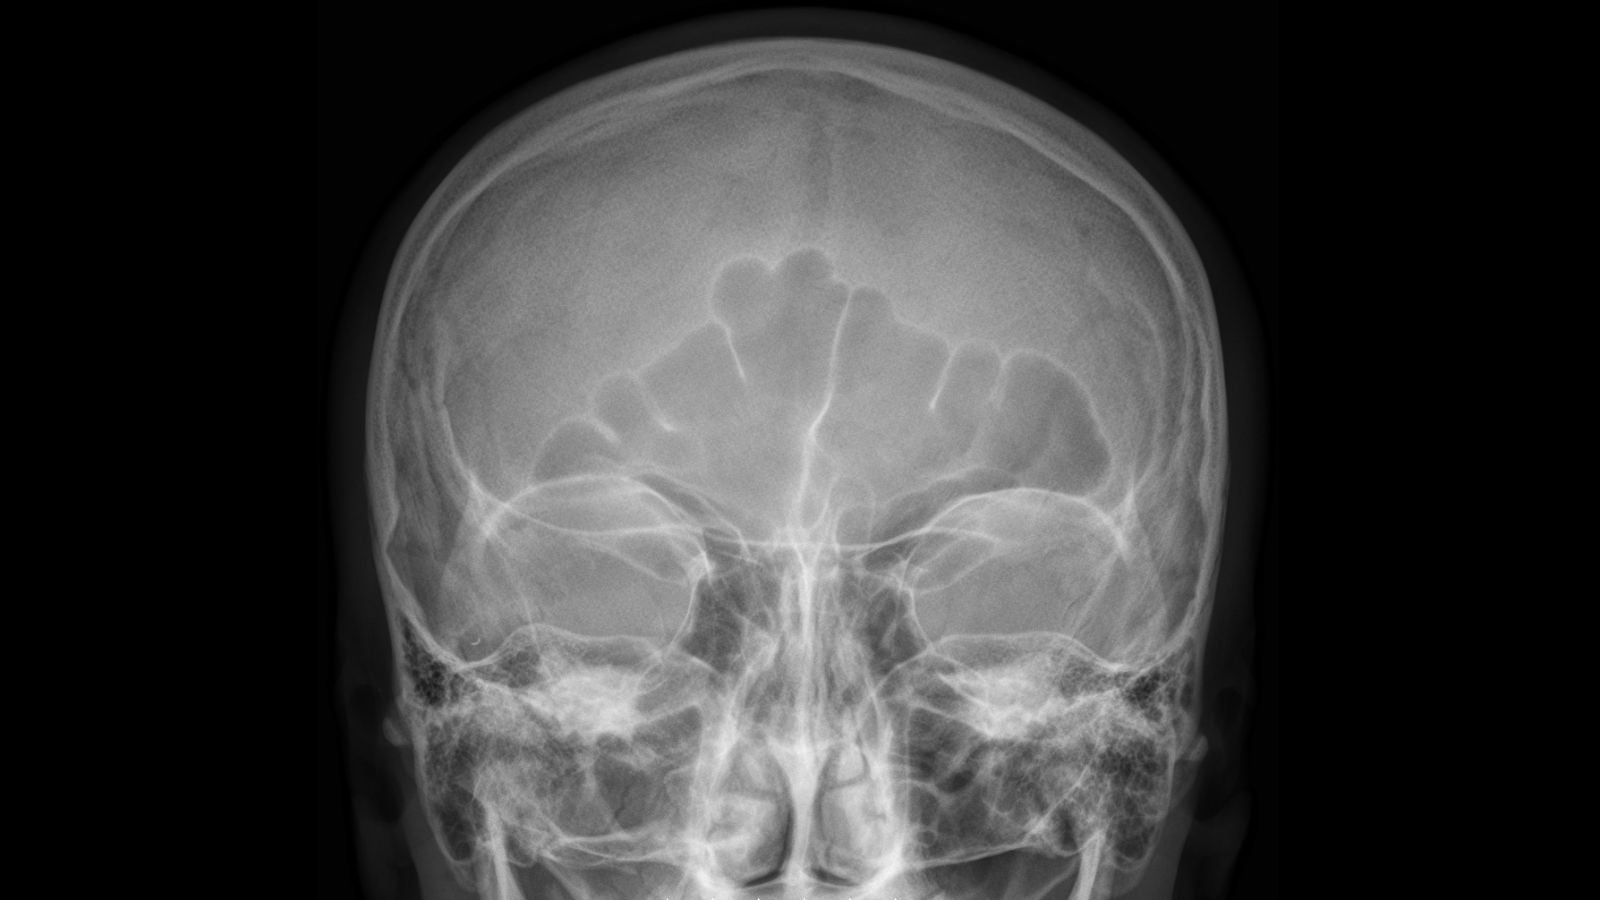

Un hombre de mediana edad acudió a un hospital para tratar unos fuertes dolores de cabeza. Cuando le hicieron una tomografía del cerebro, los médicos descubrieron un globo lleno de marihuana en su fosa nasal derecha.